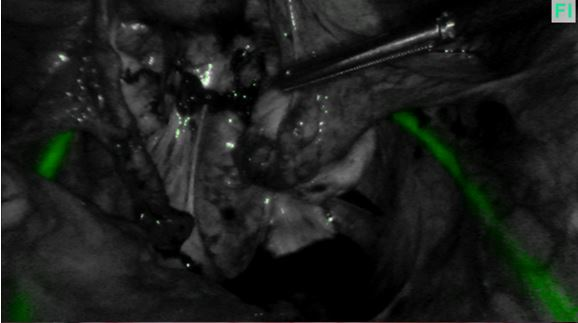

Figure 1A

Path of ureters at the start of endometriosis surgery

Figure 1B

In the past I often had to dissect out the ureter and place a rubber sloop or even consider a ureteric stent but both of these procedures can cause trauma to the ureter. However slooping will only help identifying a portion of the ureter whereas ICG can show the entire length of pelvic ureter (figures 1A and 1B below). Stenting can lead to post-operative pain and haematuria and I don’t find them particularly helpful in identifying the ureter prior to seeing the stent when you transect the ureter!